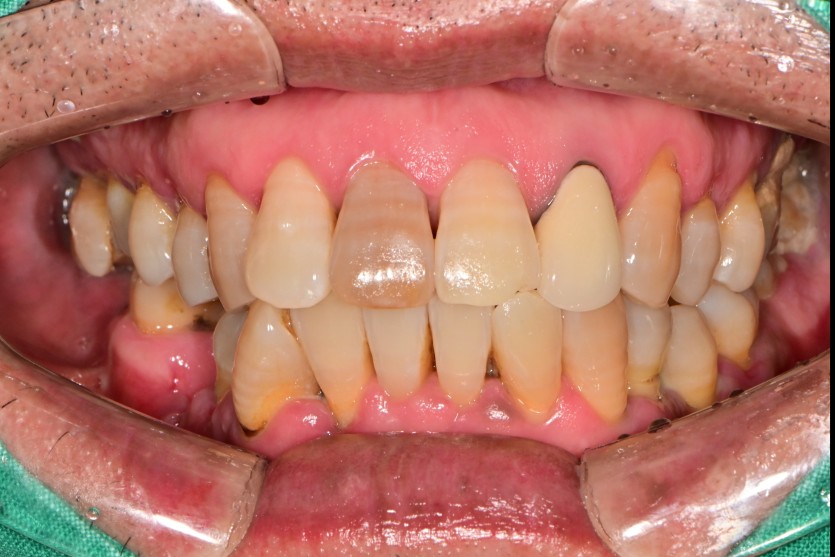

하악 전체 임플란트 증례입니다.(상악 일부)

14개의 임플란트로 완성하였습니다.